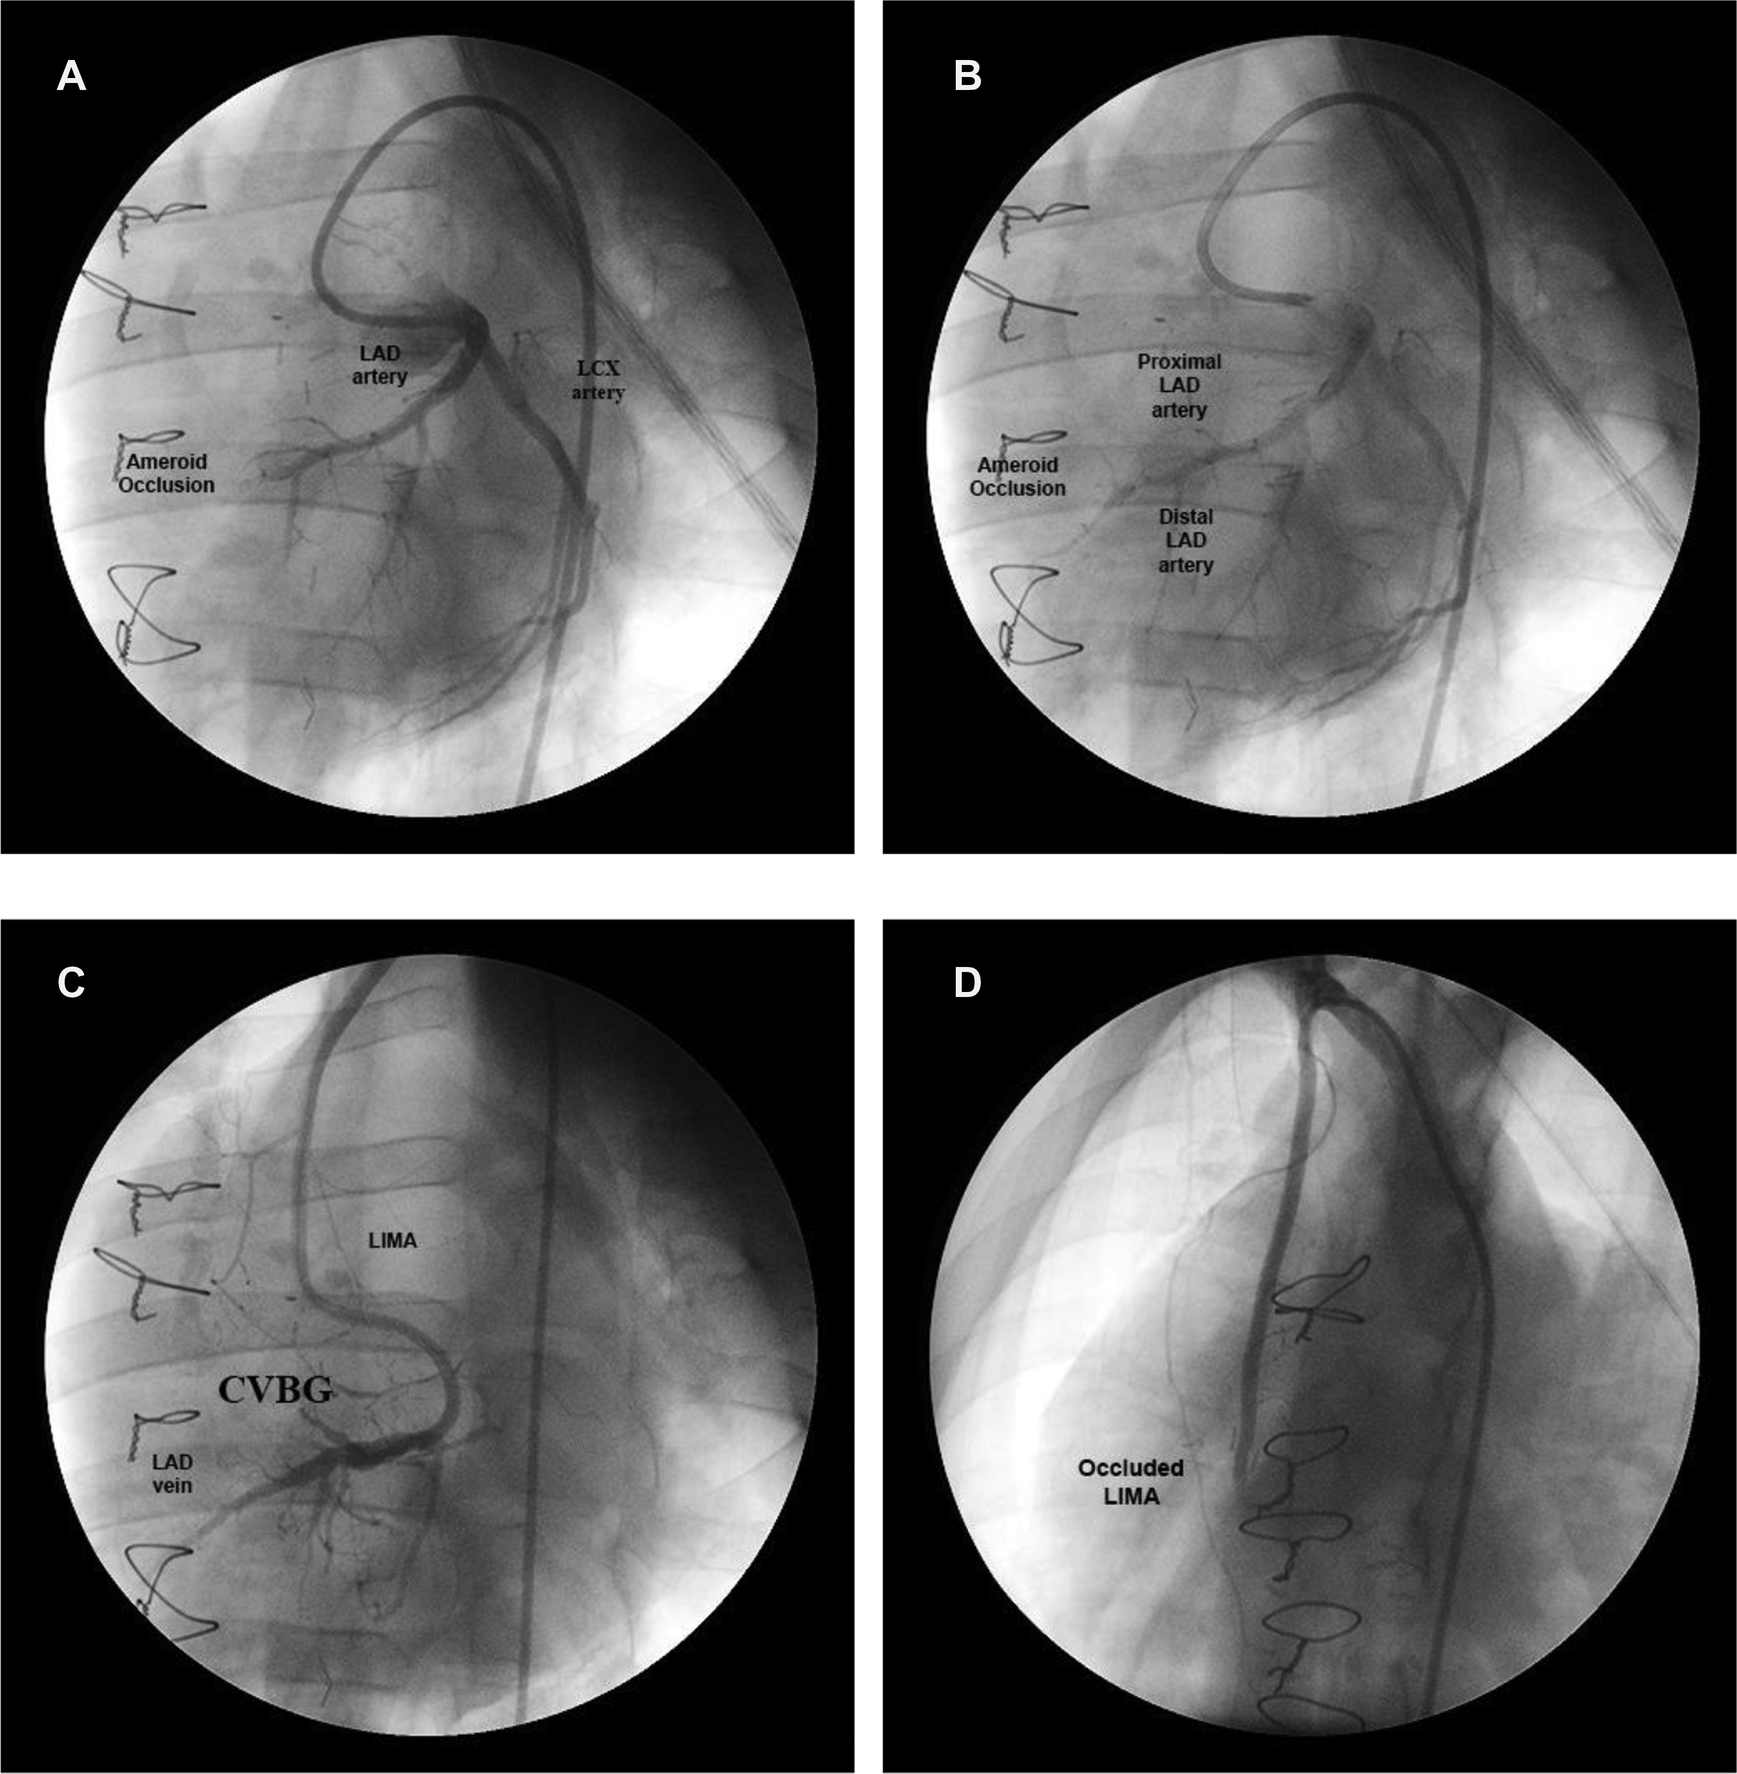

All animals had total occlusion of the LAD artery, confirmed by angiography, two weeks after ameroid placement and GCV ligation/occlusion. An angiogram of the LAD artery shows the ameroid-occluded artery during early injection of contrast material (Figure 4A), and a few seconds later (Figure 4B) after additional filling. The filling with contrast of the LAD artery distal to the ameroid occlusion indicates the presence of novel “collaterals” or connections between the native arterioles and the newly arterialized venules. Figure 4C shows the CVBG between the LIMA and the GCV two weeks after the revascularization procedure. Approximately four weeks after CVBG, occluded grafts (Figure 4D) were found in all the animals in Group I possibly due to competitive flow through the arterial-newly arterialized venous “collateralization”.

Figure 4

Coronary angiogram at different stages in a representative animal. (A) Ameroid-occluded LAD artery at early contrast injection. (B) Same artery a few seconds later after additional filling. (C) CVBG between the LIMA and the arterialized GCV two weeks after the revascularization procedure. (D) Occluded LIMA (graft failure) four weeks after CVBG.

The filling with contrast, during angiography, of the LAD artery distal to the ameroid indicates the presence of “collaterals”. At the time of CVBG, the LAD artery was completely occluded and the LIMA graft was established with substantial flow. By the third to fourth week after revascularization, the LIMA was occluded. An explanation for the graft failure may be the smooth muscle cell proliferation and intimal hyperplasia at the venous edge of the anastomosis. Another explanation may be that the competitive flow due to interconnections between the native arteries and newly arterialized veins increased the LAD artery flow substantially, and in the process competitively occluded the LIMA. In other words, flow from the LIMA is no longer necessary to sustain cardiac function, which is now restored by perfusion of the ischemic myocardium via the arterial-newly arterialized vein “collateral” vessels. This phenomenon requires 3–4 weeks in swine and was very reproducible in all the treated animals.